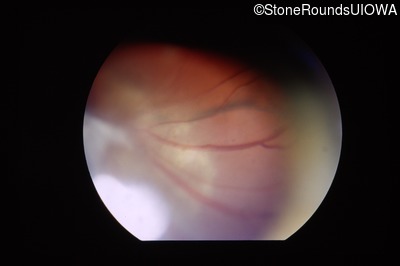

Visit at age: 4 years (Visit 2)

Fundus Photography - Left - 20/60

Exemplar